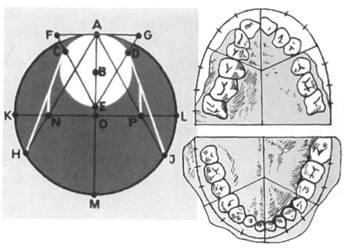

Рис. 13.25. Построение диаграммы Хау-лея—Гербера— Гербста.

ные и угловые измерения. На модели челюсти находят условную базовую точку отсчета. В качестве такой точки авторы используют точку пересечения сагиттальной и трансвер-сальной плоскостей с мезиальной поверхностью первых постоянных моляров. В диагностике применяют диаграммы, по которым определяют сумму мезиодистальных размеров трех верхних зубов. Для определения формы зубного ряда модель накладывают на чертеж так, чтобы ее средняя линия, проходящая по небному шву, совпадала с диаметром AM, а стороны равностороннего треугольника FEG проходили между клыками и премолярами. Затем тонко заточенным карандашом обводят контур зубного ряда и сравнивают имеющуюся форму с кривой диаграммы (рис. 13.25).